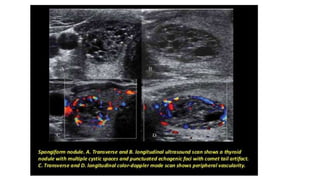

US image of a thyroid nodule (arrowheads) containing multiple fine punctuate echogenicity's

(arrow) with no comet-tail artifact, indicating high suspicion for malignancy. FNA and surgery confirmed PTC. (Reproduced from Frates MC.

Management of thyroid nodules detected at US: Society of Radiologists in Ultrasound consensus conference statement. Radiology2005;237:794–800;

with permission.)

US image ofa thyroid nodule (arrowheads) containing multiple fine punctuate echogenicity's (arrow) with no comet-tail artifact, indicating high suspicion for malignancy. FNA and surgery confirmed PTC. (Reproduced from Frates MC. Management of thyroid nodules detected at US: Society of Radiologists in Ultrasound consensus conference statement. Radiology2005;237:794–800; with permission.)